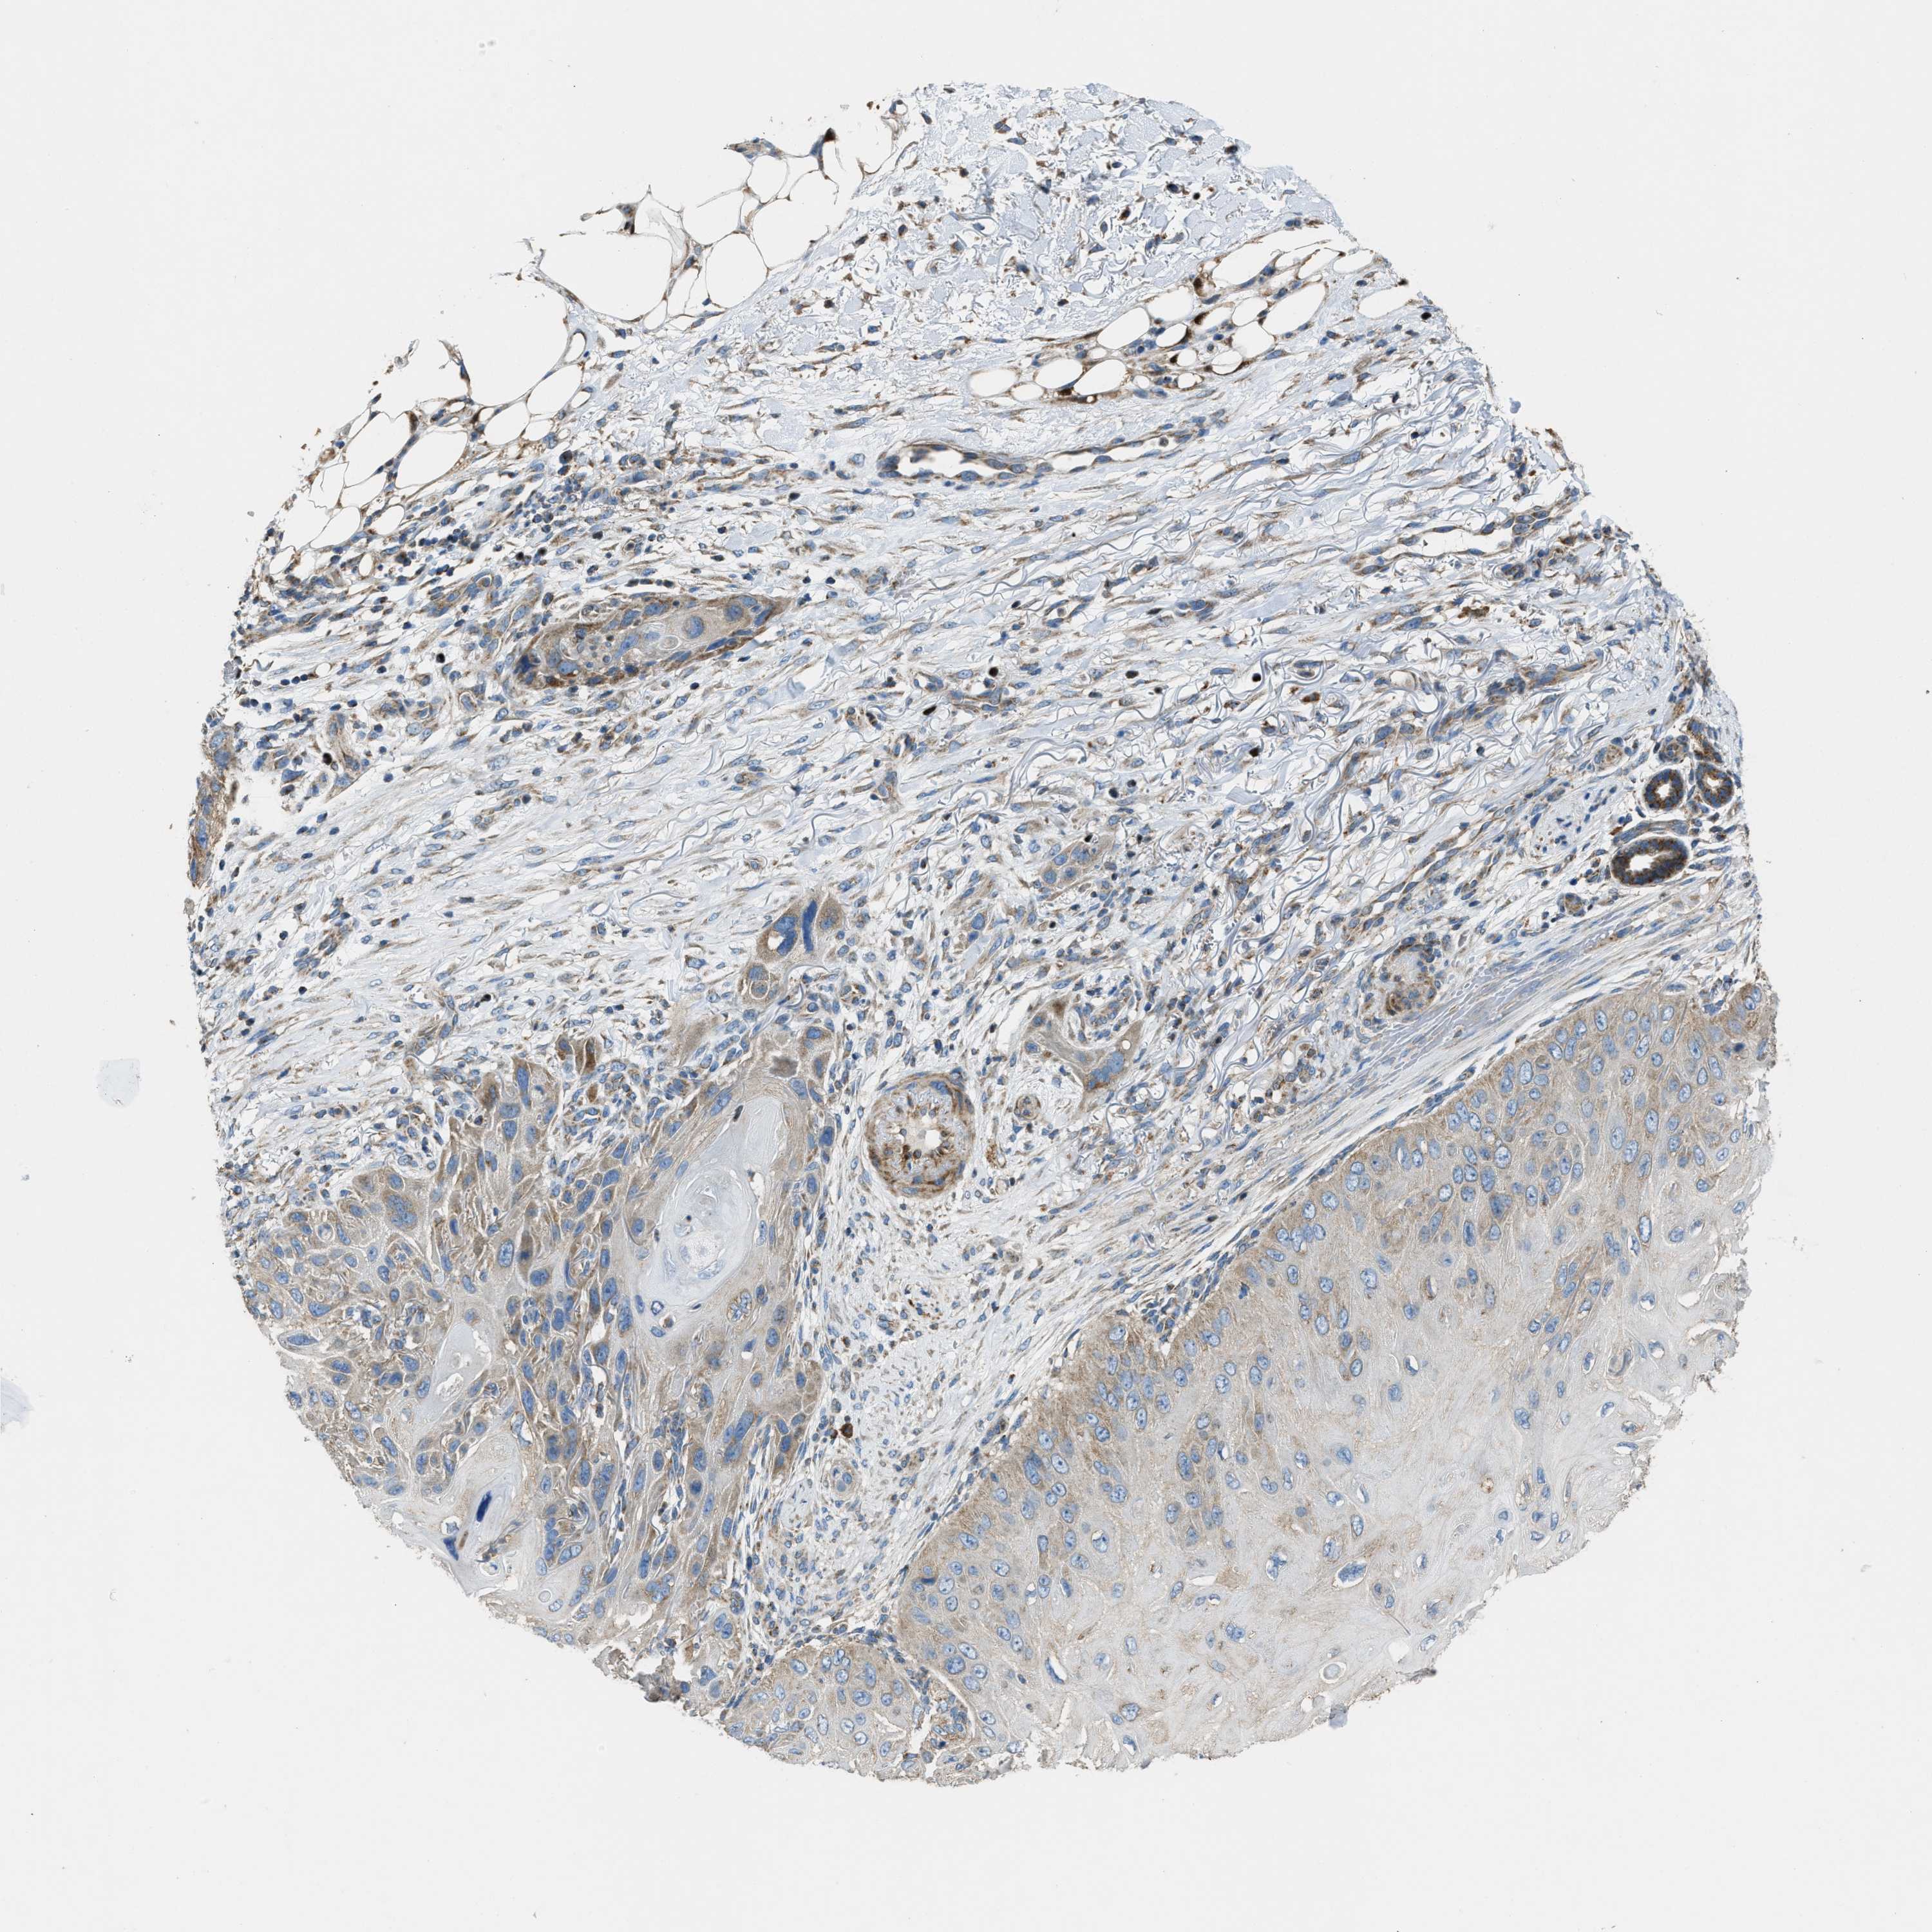

Basal cell and squamous cell cancer

SKIN CANCER - Protein expressioni

A mouse-over function shows sample information and annotation data. Click on an image to view it in a full screen mode. Samples can be filtered based on level of antibody staining by selecting one or several of the following categories: high, medium, low and not detected. The assay and annotation is described here.

Antibody stainingi

Antibody staining in the annotated cell types in the current human tissue is reported as not detected, low, medium, or high, based on conventional immunohistochemistry profiling in selected tissues. This score is based on the combination of the staining intensity and fraction of stained cells.

Each image is clickable and will lead to virtual microscopy that enables deeper exploration of all samples and also displays staining intensity scores, fraction scores and subcellular localization as well as patient and tissue information for each sample.

Antibody HPA021167

Staining

High

Medium

Low

Not detected

Intensity

Strong

Moderate

Weak

Negative

Quantity

>75%

75%-25%

<25%

None

Location

Nuclear

Cytoplasmic/membranous

Cytoplasmic/membranous,nuclear

Squamous cell carcinoma, NOS